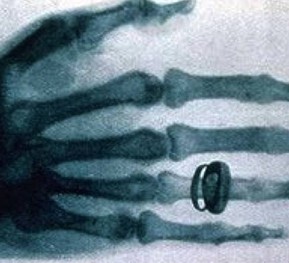

X光機(jī)主要是由X光機(jī)電源,X光球管以及控制電路等組成,是產(chǎn)生X光的設(shè)備,目前已廣泛應(yīng)用于醫(yī)院協(xié)助醫(yī)生診斷疾病,工業(yè)的無損探傷,科學(xué)教育,機(jī)場(chǎng)和火車站的安全檢查等

圖像監(jiān)控法是直接從x射線透視圖像構(gòu)形來判斷物品的,因此,被檢物是否可疑,取決于監(jiān)視器或顯示器上的圖像。顯示器或監(jiān)視器上出現(xiàn)的不常見物或異形物,都應(yīng)視為可疑物品。那些不能準(zhǔn)確辨認(rèn)的物品也應(yīng)視為可疑物品,需仔細(xì)觀察,根據(jù)需要可將圖像定位分析。